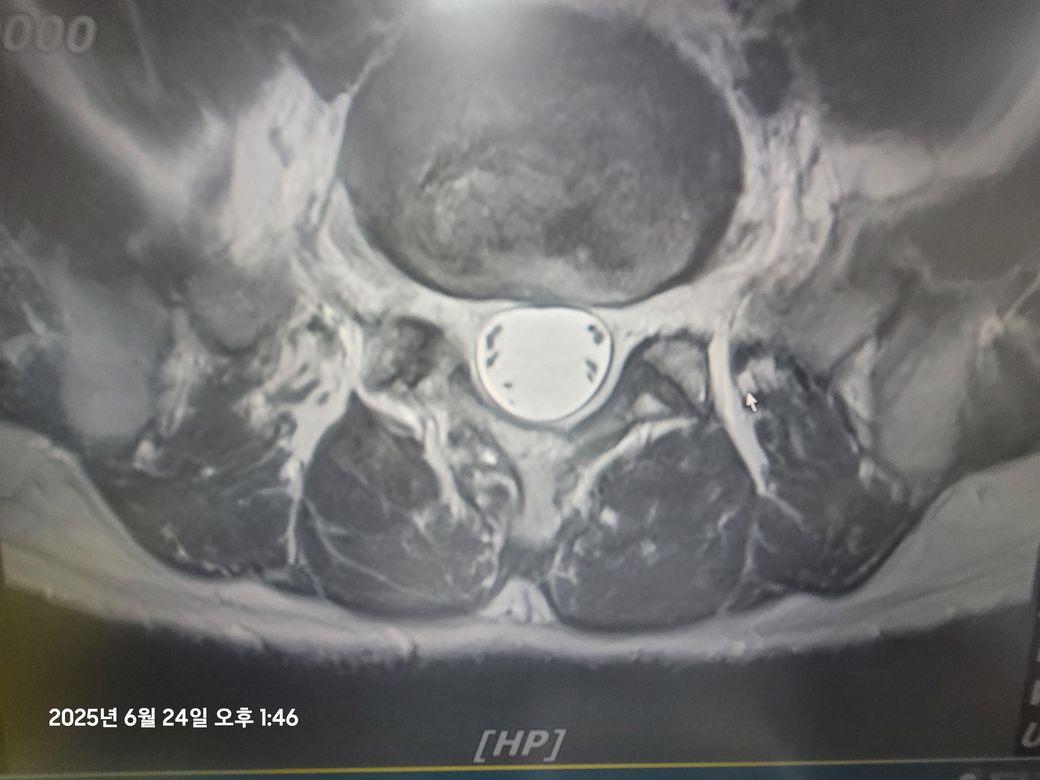

• 4번 째 사진